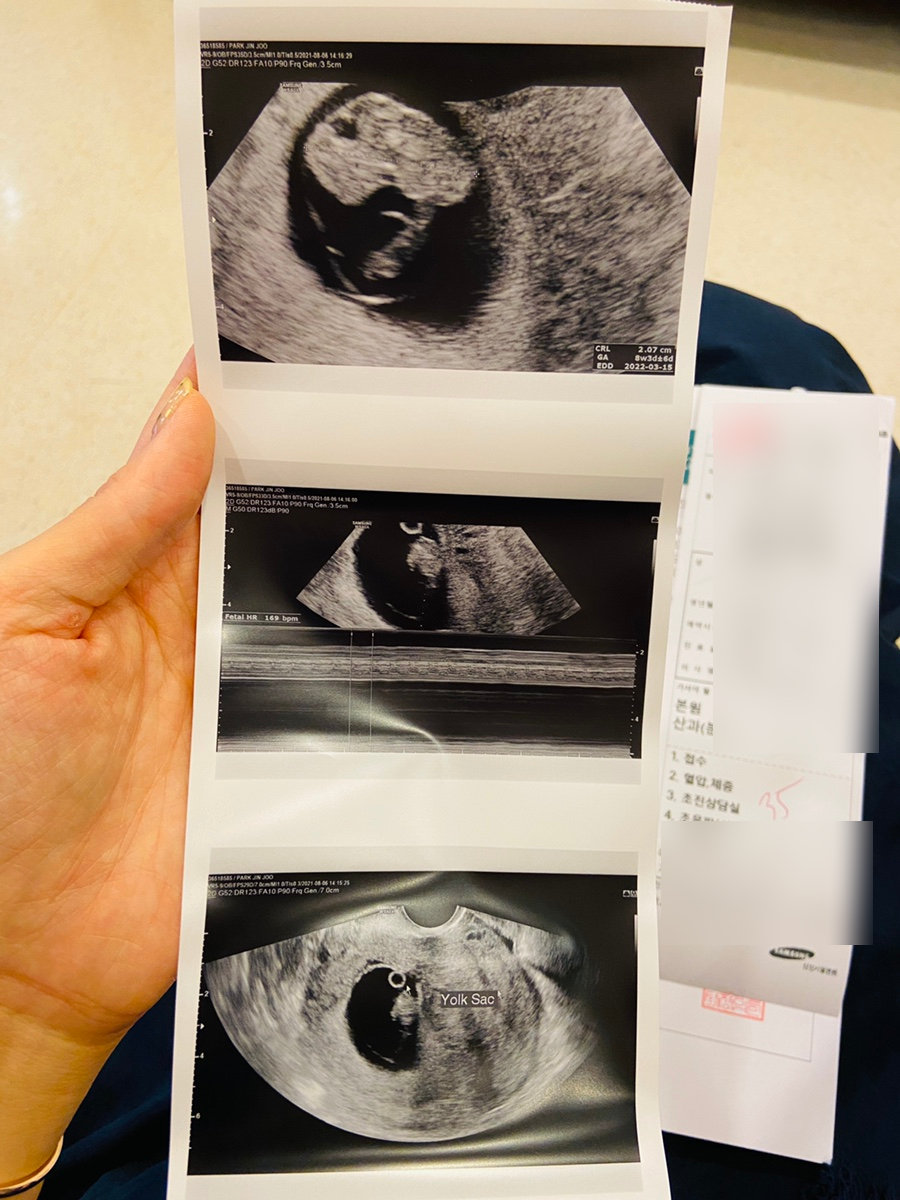

이제 임신 8주차 시작!!

배아였던 따복이는 태아가 되었어요. www

280days 어플로는… 8주차가 제일 귀여운 것 같아요 www

정말로 너무 귀여워ㅜㅜ

보름달이 뜨면… 아기 캐릭터가 좀… 원숭이 같았는데 지금은 너무 귀여워요.~~

8주 3일째인 8월 5일. 송파 마리아플러스 진료가 있어서 다녀왔습니다 🙂

정재훈 원장님이 방학이라 이경희 과장님 진료 받았어요~5층은 처음 가봤는데 2층보다 좋더라고요 대기 공간도 더 넓고 되게 돼있고.. 진료실 안에.. 초음파 보는 모니터도 정면에 하나 더 있어서 편했어요!

따복이는… 머리 엉덩이 길이 1.91cm 심장 소리 166bpm으로 아주 잘 자랐어요.